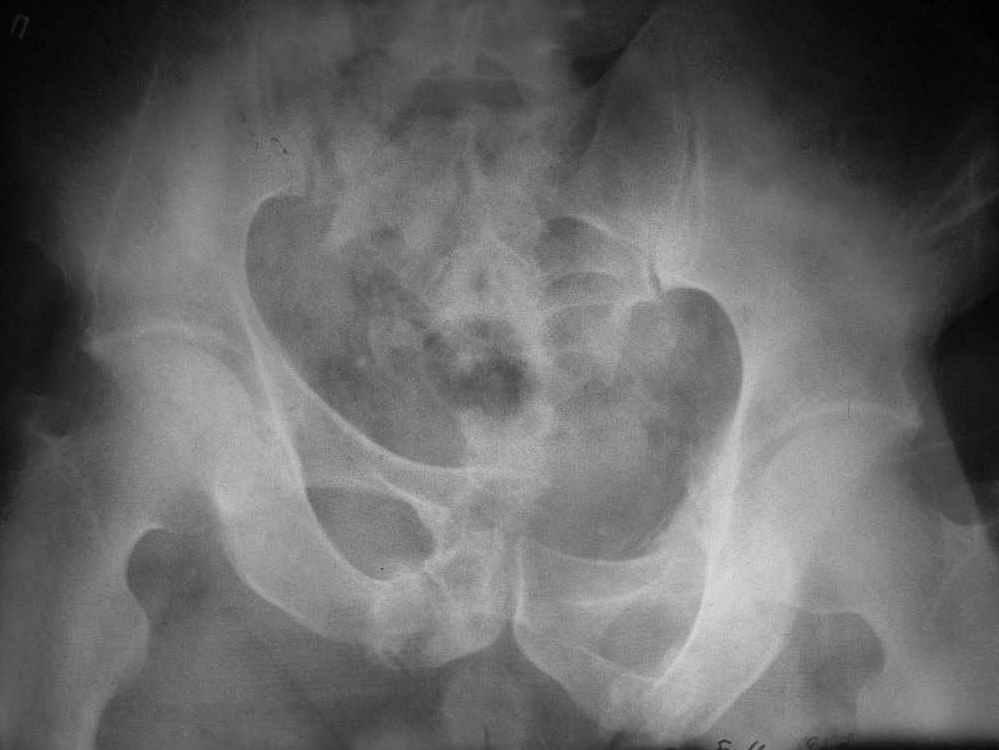

По прямой проекции - Вертикальная стабильная (?) деформация таза IIIст., неправильно сросшийся (?) перелом боковой массы крестца справа, неправильно сросшийся поперечный (?) перелом првавой вертлужной впадины.

Исходная картина